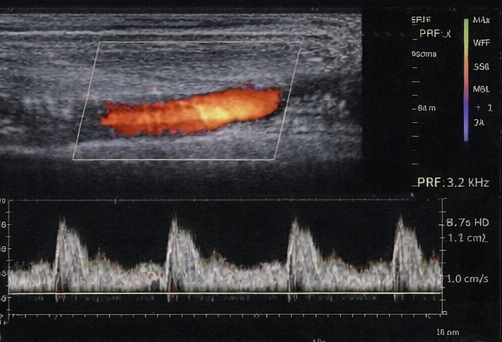

Duplex Doppler ultrasound of the lower limbs demonstrated mild peripheral arterial disease with preserved distal flow. There was no critical limb ischemia.